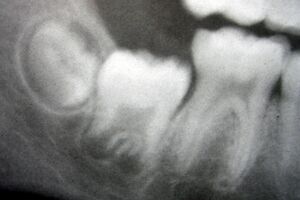

Radiograph of lower right (from left to right) third, second, and first molars in different stages of development

X-ray of teeth of a boy aged 5 years showing left lower primary molar and developing crowns of left lower permanent premolar (below primary molar) and permanent molars